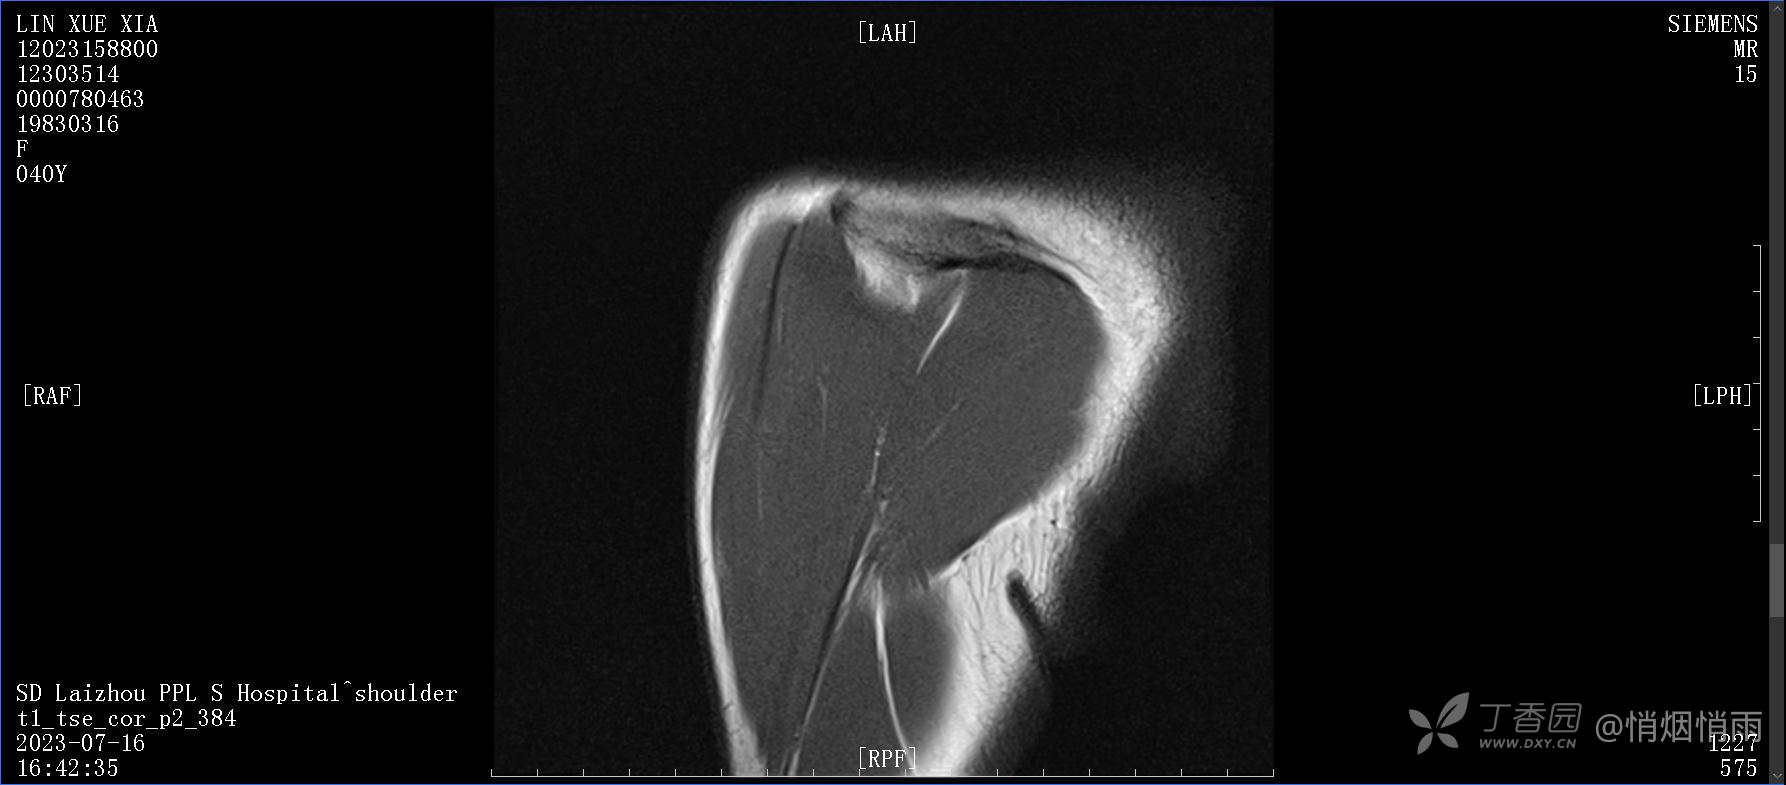

查体:右肩关节局部轻度肿胀,肩胛区压痛明显,痛处不固定,肩关节痛性活动受限,jobe test(+),lift -off test(+),中指、环指感觉较余指减退,余肢端感觉及血运情况可。

目前的诊断,暂时依据辅助检查诊为肩袖损伤,但是患者疼痛的性质和特点,却不是单纯的肩袖损伤所致。考虑过胸廓出口综合征,但是该疾病会出现肩胛区的疼痛吗?(由于考虑到费用的问题,没再进行下一步的检查)带状疱疹会有如此的症状吗?